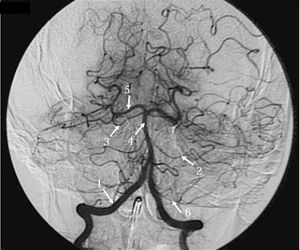

Can you identify each of the numbered arteries?

1-Vertebral a. 2-AICA 3-Superior Cerbellar a 4-basilar a. 5-Posterior cerbral a 6-PICA i think

Its exactly right or wrong i don't known 1.internal carotid artery 2. Posterior cerebral artery 3.rt mca 4. Anterior communicating antery 5. Mca 6.posterior cerebral artery

1-vertebral artery ( first branch of the first part of the subclavian artery.,,,, pass through the foramen transversarium of cervical vertebra ,except C7 vertebra.) 2.anterior inferior cerebellar artery 3.superior cerebellar artery 4.Basilar artery ( pass through the basilar groove of pons) 5.posterior cerebral artery (terminal branch of basilar artery) 6.posterior inferior cerebellar artery ( branch of the vertebral artery)